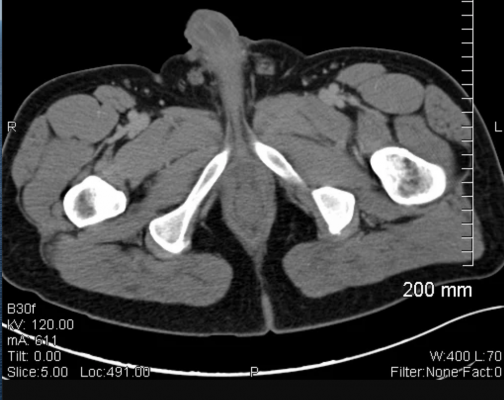

In order to be eligible for NRG-RTOG 0526, prostate cancer patients needed to have low or intermediate risk prostate cancer prior to EBRT in addition to having a proven LR thirty or more months following their EBRT. 92 patients were analyzed for the study and followed for a minimum of 5 years after their salvage brachytherapy. Participants on NRG-RTOG 0526 received a minimum dose of 140 Gy with I-125 or 120 G with Pd-103. Researchers followed clinical outcomes at 5 year or greater including objectives such as disease-specific survival, overall survival, time to biochemical failure, and patterns of recurrence.

As initially reported, 14% of participants experienced late Grade 3 gastrointestinal and genitourinary AEs at a median follow up of 6.9 years. The median prior EBRT dose was 74 Gy and the median interval since EBRT was received was 85 months. Androgen deprivation therapy was combined with salvage BT in only 16% of cases. The 5-year freedom from biochemical failure rate was 68%, which is comparable to other salvage modalities. At 10 years, the biochemical failure rate was 54% (95% CI: 43-66). Disease-free survival at 5 years was 61% but fell to 33% at 10 years. Nineteen patients died. Four patients had local recurrence (5% at 10 years), and 14 had distant failure with a 10-year rate of 19% (95% CI:10-29). None of the clinical or treatment factors was significantly associated with participants' overall survival, disease-free survival, or local, distant, or biochemical failure.